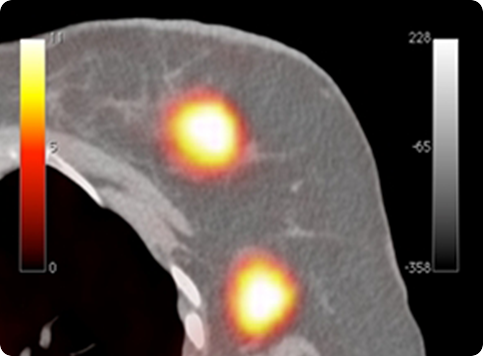

Figure 13

Clear-PEM and the corresponding whole-body PET/CT exams. Tumors not seen on PET/CT are identifiable using PEM (data collected at Hospital Nord - Marseille).